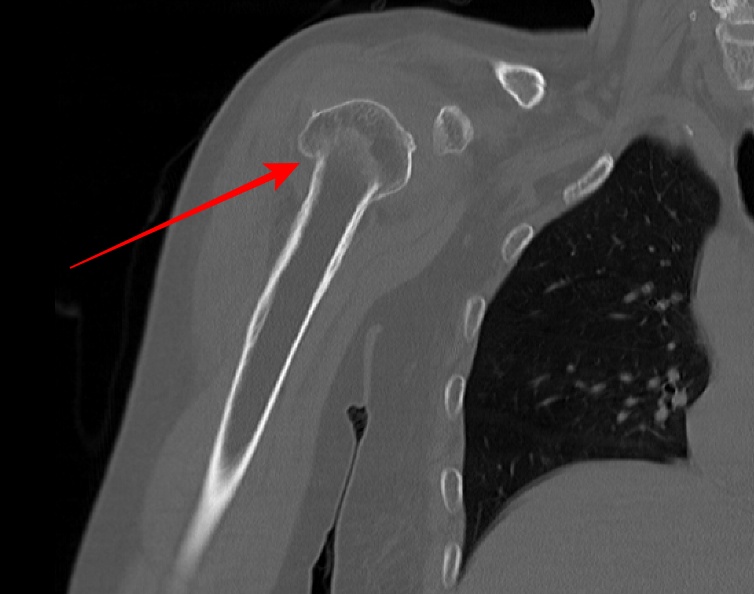

- Rt Shoulder CT

- surgical neck Fx 의심 되어 검사 의뢰됨.

- 붉은색 화살표가 골절된 부위다.

displaced neck fracture of humerus with impaciton